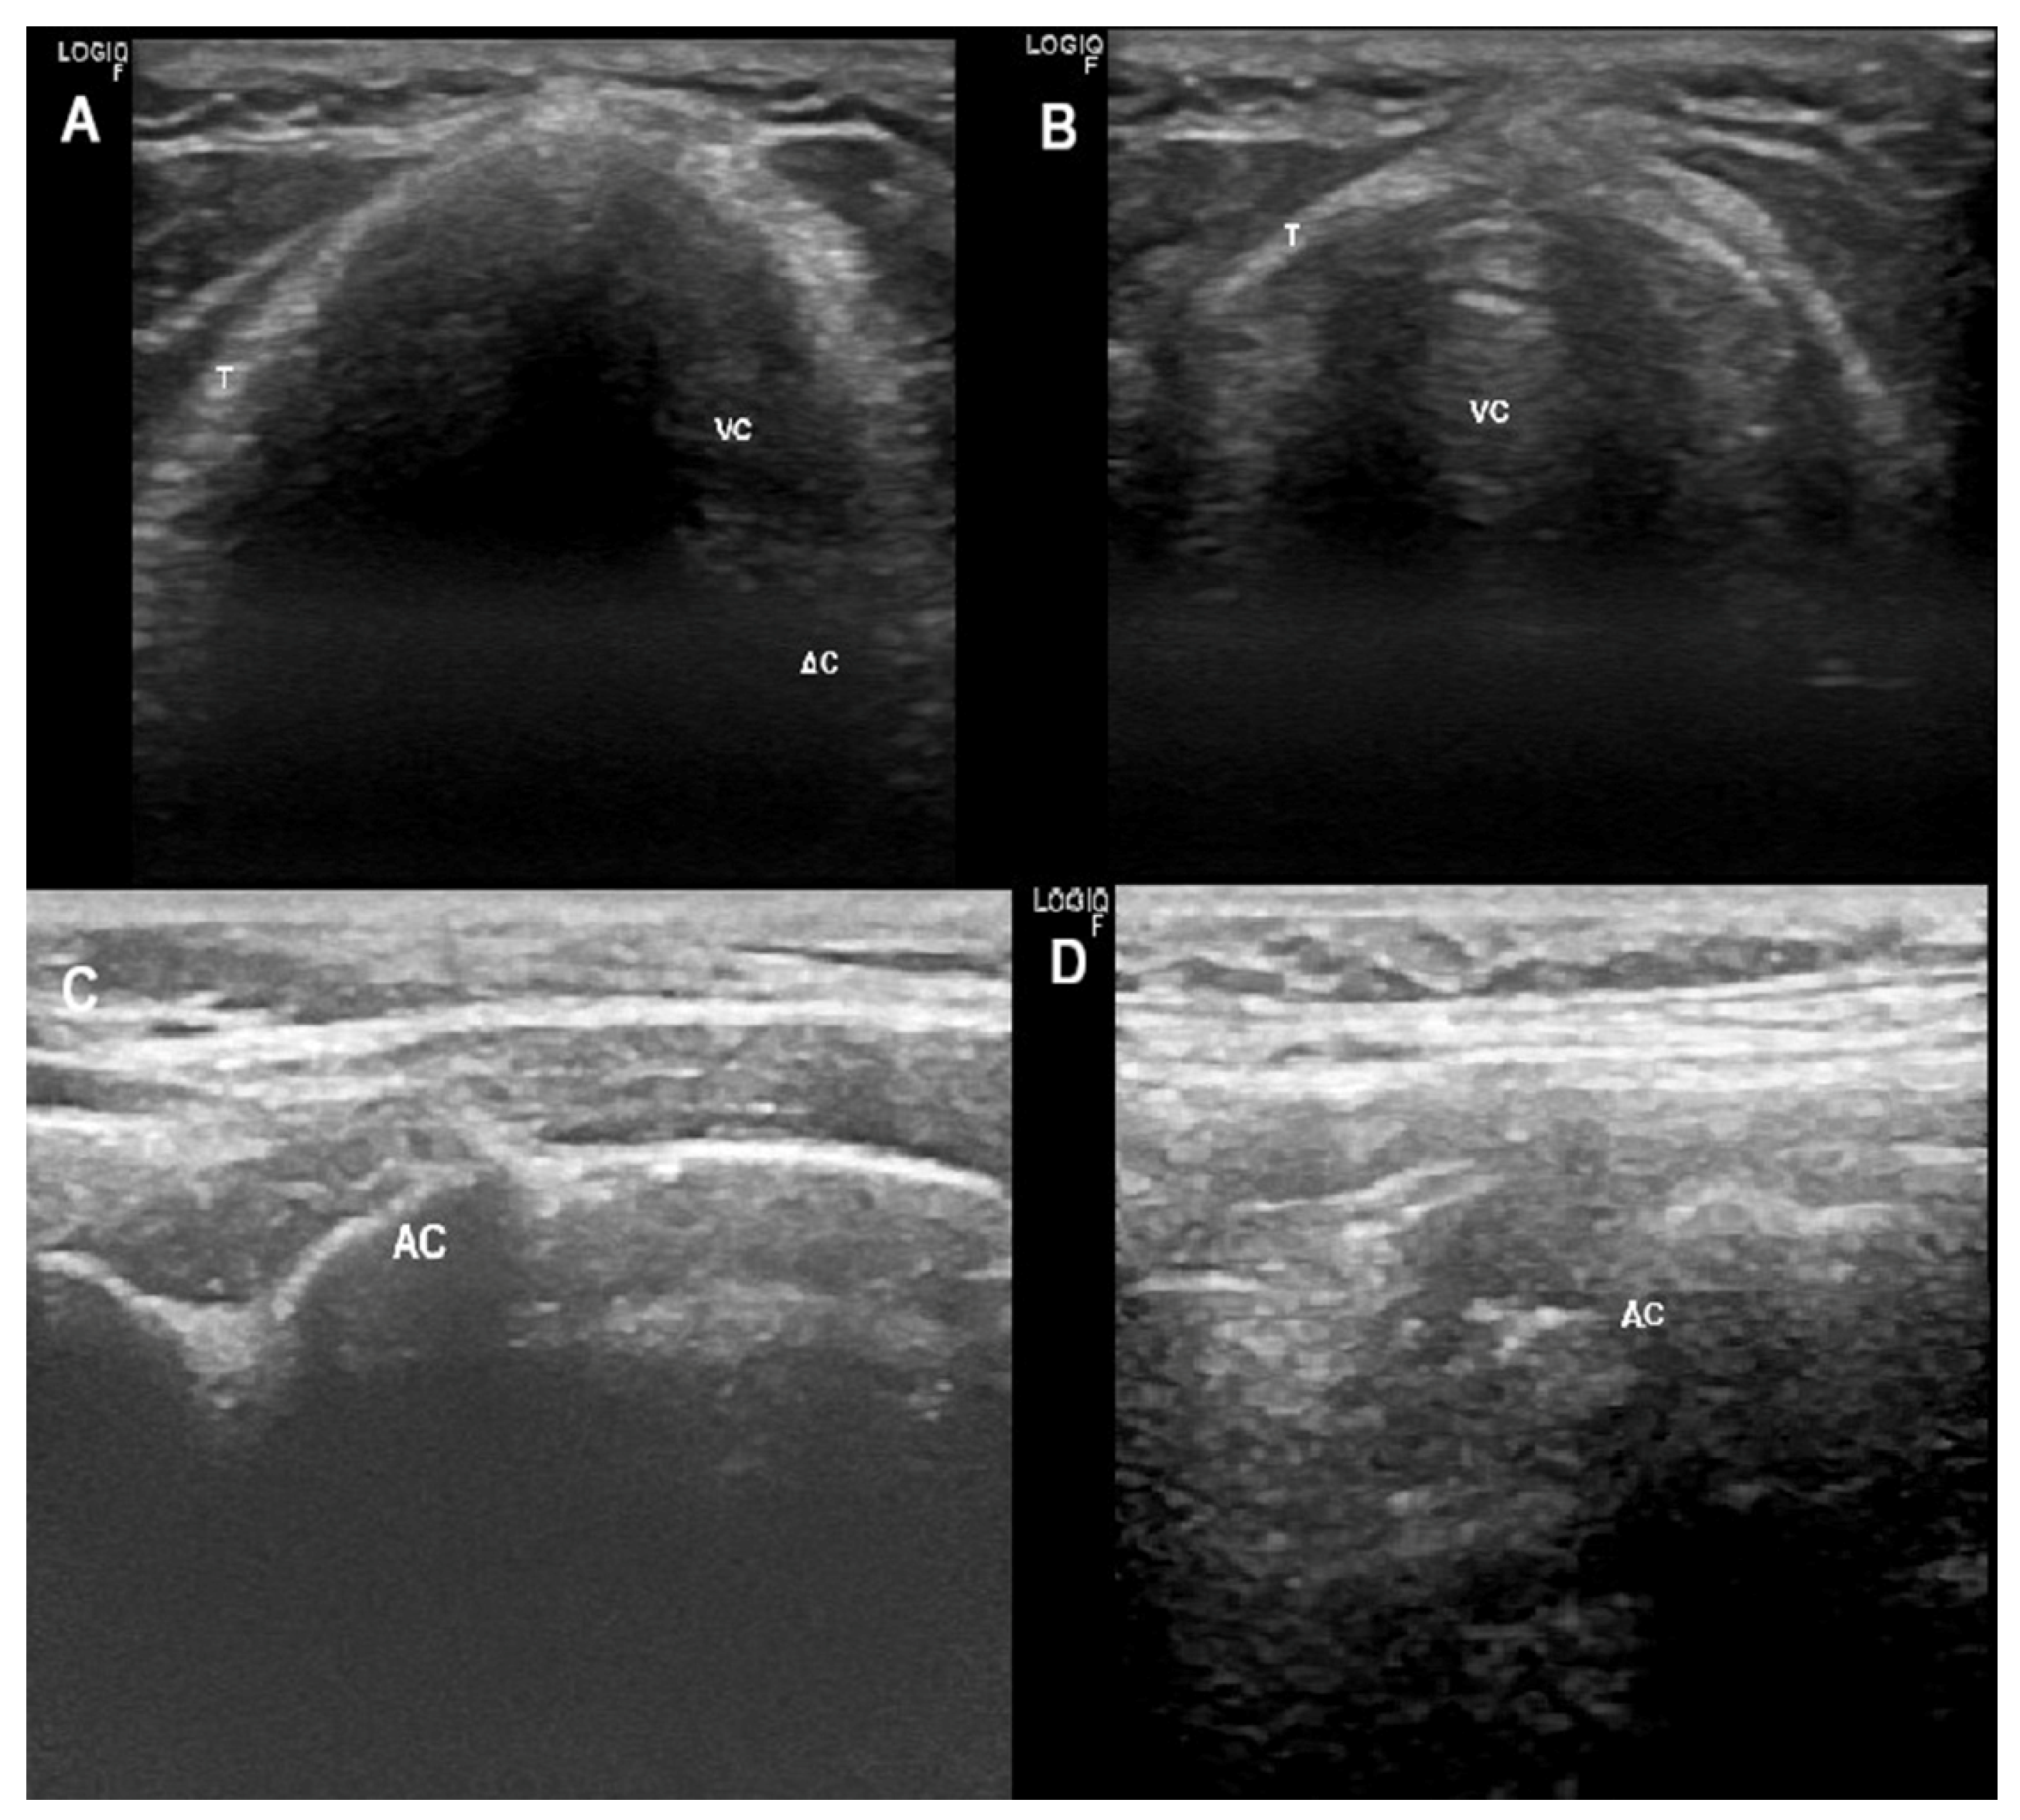

2.7.1. Ultrasonographic Upper Airway Structures

Glottis

Supra-Glottis

Oropharynx